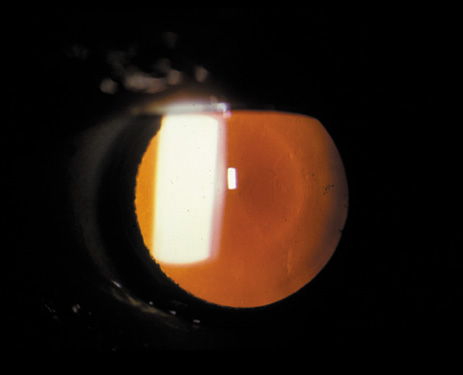

Nuclear cataracts tend to progress slowly. The refractive index of the lens changes as the nucleus progressively hardens, which usually results in increasing myopia.20,21 In some patients this is accompanied by optical distortion, especially of distant images, while near vision remains unaffected. A nuclear cataract is best seen with the narrow-beam direct illumination employed by the slit-lamp, which reveals the color and generalized haze or opalescence of the nucleus. In the early stages, the two halves (cotyledons) of the embryonic nucleus remain visible (Fig. 3). Later the entire nucleus appears as a homogeneous mass in contrast to the cortex (Fig. 4). Retroillumination may show the “oil droplet” effect (Fig. 5). Sometimes one may notice crystals in the lens nucleus (known as a Christmas tree cataract; Fig. 6A and B).

Fig. 3. Early nuclear cataract. Note the “cotyledons” in the nucleus.